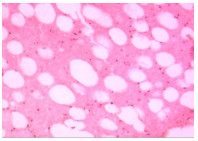

检查无手术禁忌证后,患者于急诊行右心腔异物清除术,全麻成功后,经食管超声心动图检查示:右心腔内见长条形强回声,跨三尖瓣,自右房延伸至右室心尖部。切开右房,见一白色异物,质地硬,右房侧头端稍锐利,未划破右房壁,另一端与右室粘连,难以拔除。行心脏停跳,停跳后探查发现,异物另一端与三尖瓣瓣下乳头肌粘连,剥离后完整取出,为白色7.5~8.0 cm长棍状物体,直径约4 mm(图 3)。反复探查右心腔无异物残留,肺动脉无异物,心脏表面无破口,行心脏复跳。病理检查示:血栓内见脂肪、胶原化的纤维组织及灰褐色无定形物质(图 4)。术后诊断:心脏异物(考虑骨水泥)。术后患者恢复良好,术后2周患者病情稳定,予以出院。

| 图 4 患者病理图像(HE染色) |